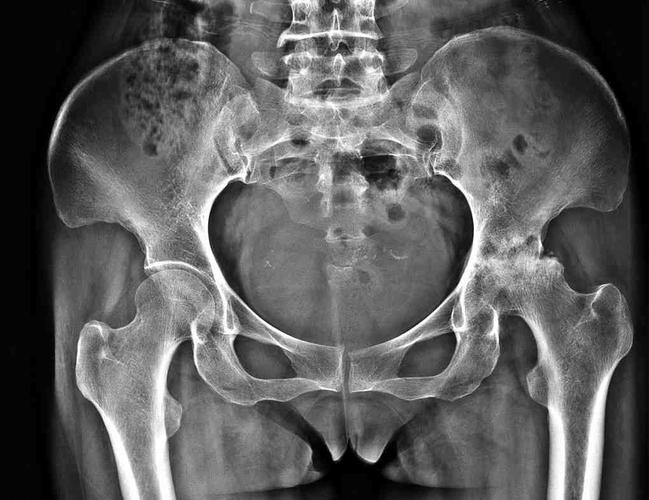

有上述病史,X光片有骶髂关节炎征象,HLA_B27 十 ,即证实为脊柱病;进一步排除牛皮癣、炎性肠病或Reiter综合征关节炎,即可作出原发性AS的诊断,而不要等到脊柱明显强直时才明确诊断。

根据上述临床标准及骶髂关节炎X线改变分级。

(1)确诊AS为:①双侧骶髂关节炎Ⅲ或Ⅳ级,同时至少有上述临床标准中之一项者;②单侧骶髂关节炎Ⅲ或Ⅳ级,或双侧骶髂关节炎Ⅱ级,并具备临床标准第Ⅰ项,或具备临床标准第2项第3项者。

(2)可疑AS为:双侧骶髂关节炎Ⅲ或Ⅳ级,但不具备任何一项临床标准者。 特发性脊柱侧凸的相关你好,有一些强直性脊柱炎患者并不表现为明显的炎性腰背痛,可能主要表现为下肢不对称的滑膜炎。建议你进一步观察病情变化,必要时查骶髂关节磁共振